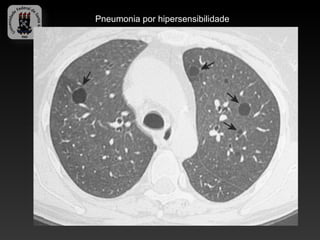

-PNEUMONIA POR HIPERSENSIBILIDADE

-Ampla gama de antígenos que causam reação imunológica.

-Histopatologia da PH: granulomas mal definidos, bronquiolite e alveolite.

-Pulmão do fazendeiro

-Pulmão do criador de aves

-Pulmão do catador de cogumelos

-Bagaçose

-Pulmão do ar condicionado

-Pulmão do lavador de queijo

-Pulmão do trabalhador do malte

-Doença da casca do bordo …

-Achados da TC:

-Opacidades em vidro fosco

-Nódulos centro-lobulares predominantemente nos terços médios e

superiores.

-Atenuação em mosaico.

-Cistos pulmonares também podem estar presentes

-A forma crônica caracteriza pela fibrose.